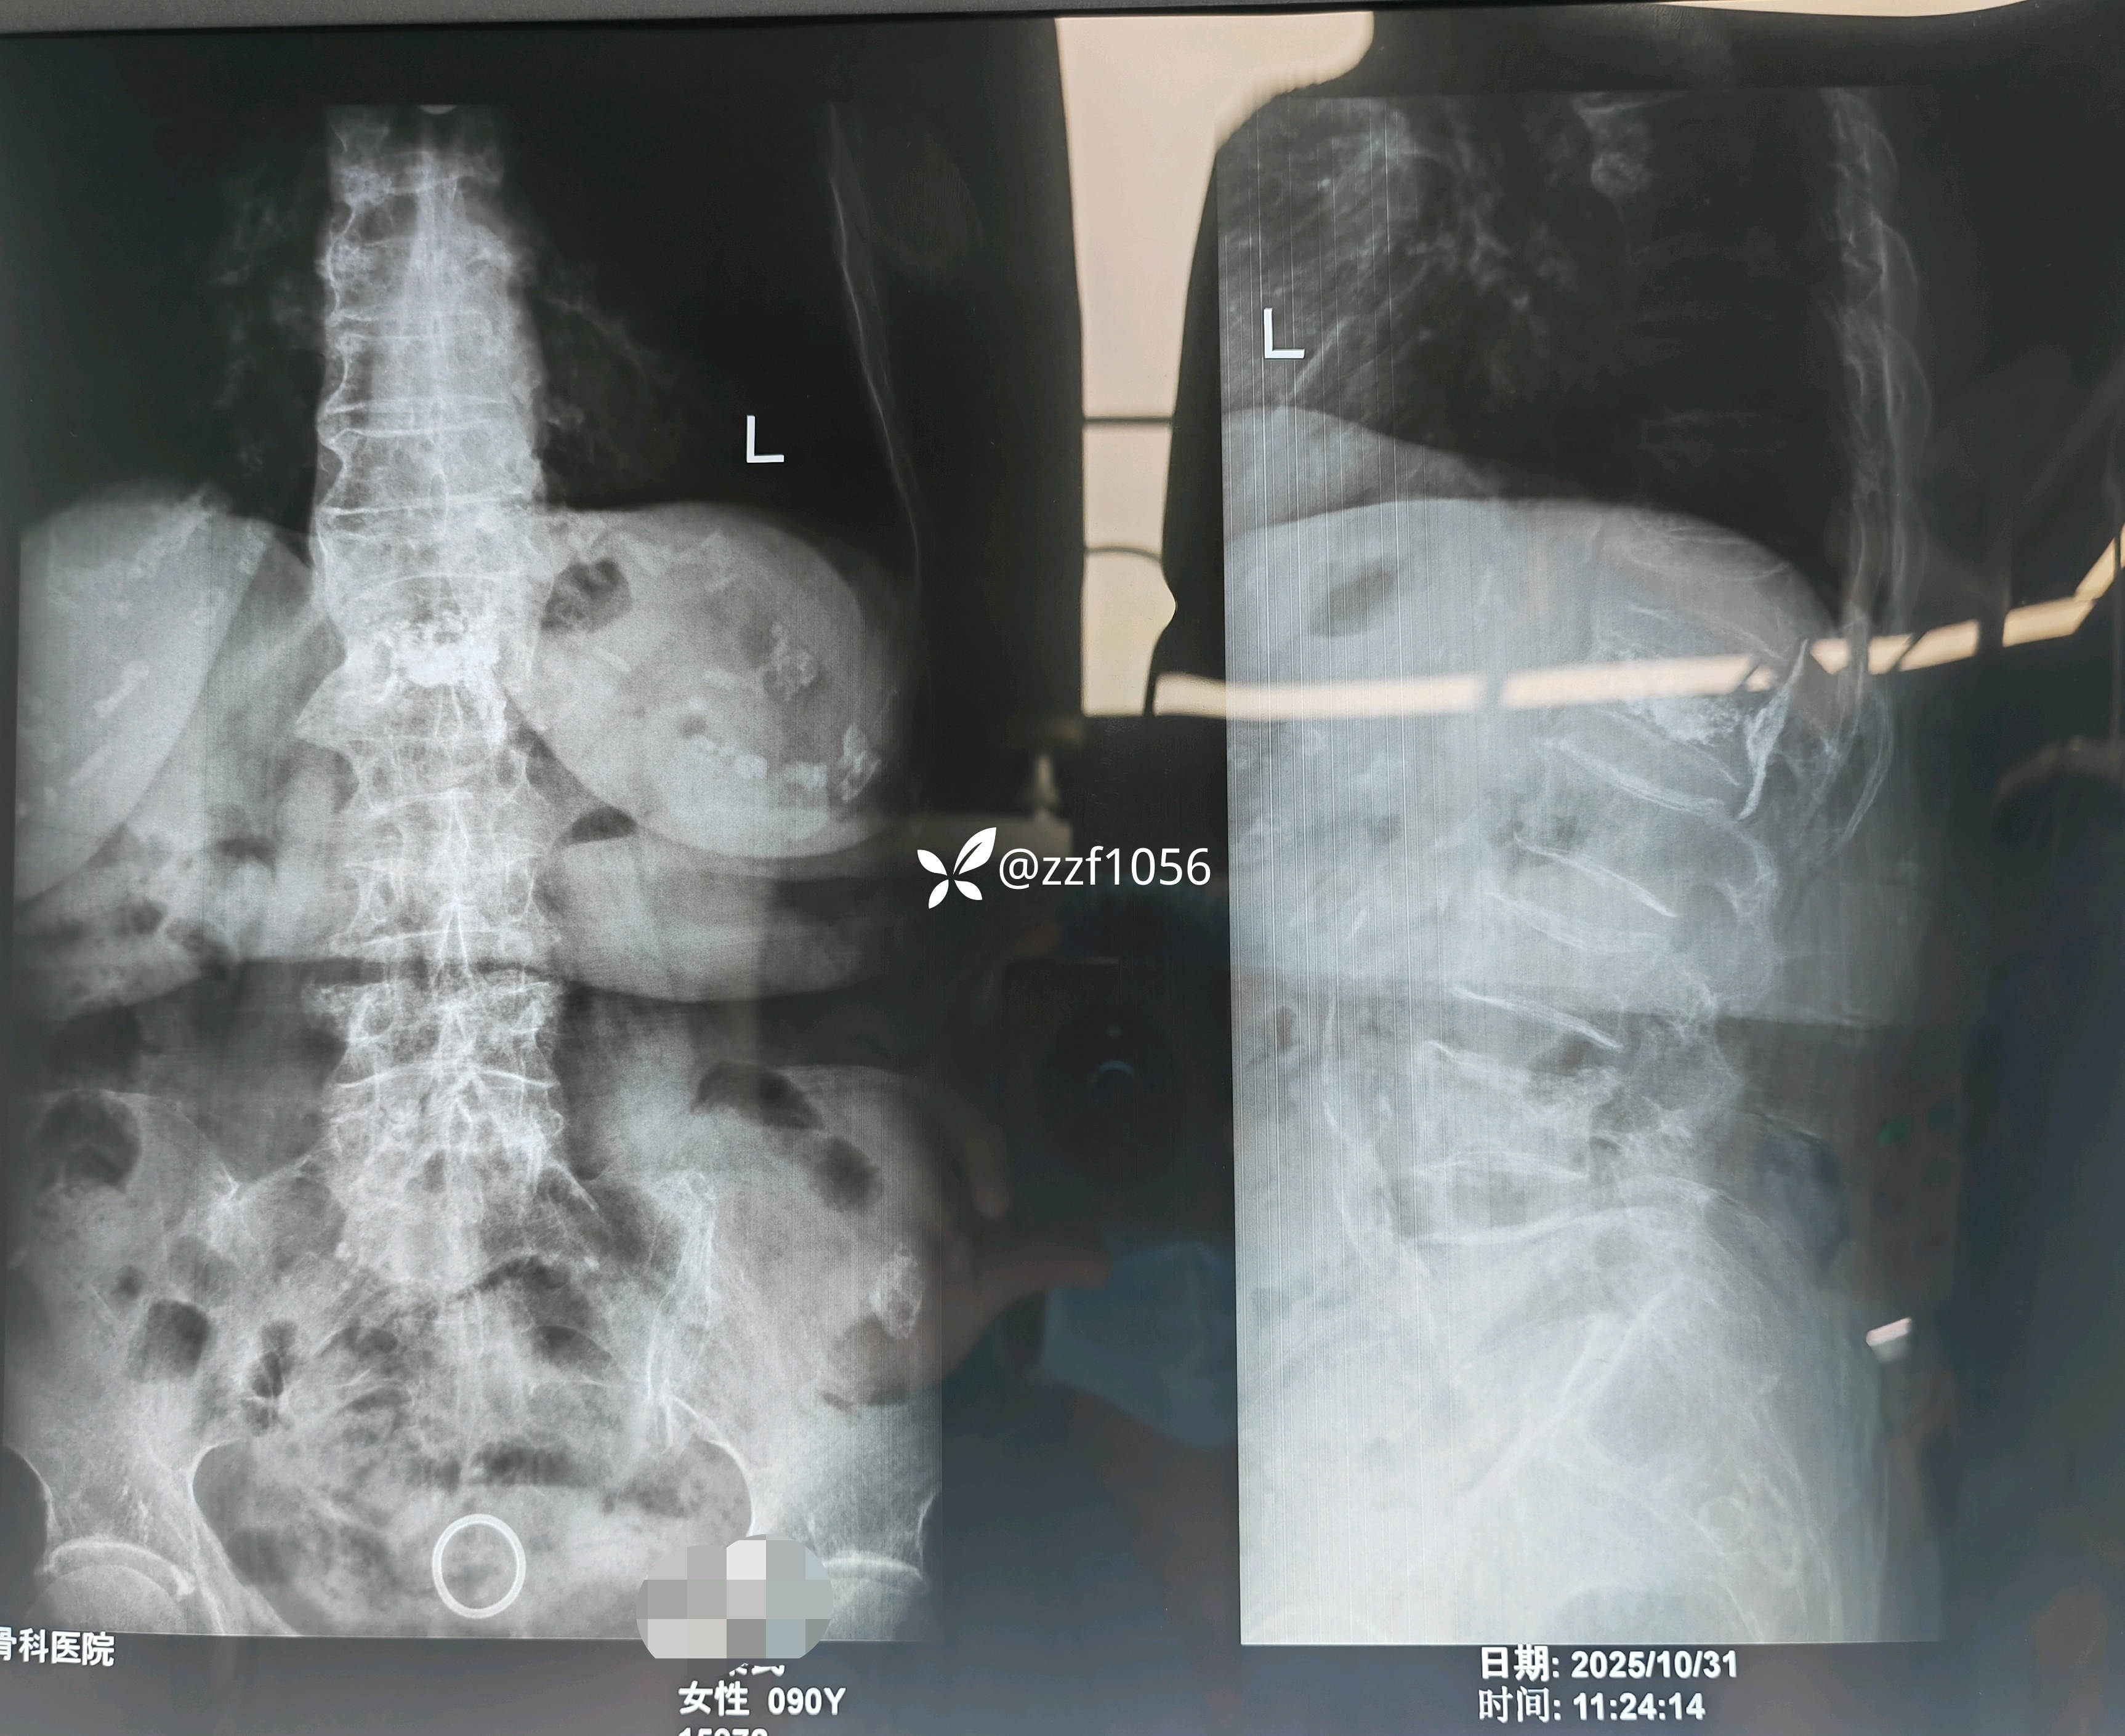

患者90岁,女,腰背疼痛3天。

门诊摄片考虑下腰椎新鲜压缩骨折,建议进一步核磁共振检查,家属拒绝配药离院。

腰3腰4椎体压缩性骨折明确